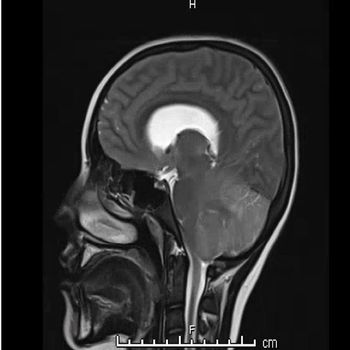

Case Studies